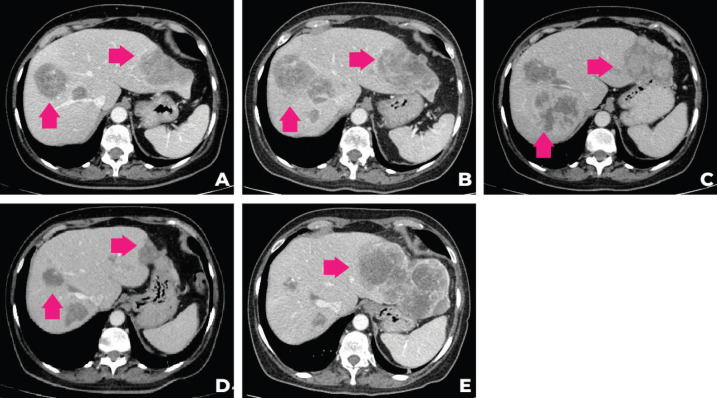

考虑到患者的临床病程和多基因检测包的结果,MTB 第二次会议讨论建议进行肿瘤靶向药物基因检测850的遗传咨询,并开始使用他拉唑帕尼进行全身治疗。 遗传咨询后,进行了 33 个基因组,包括与结肠癌、妇科癌和结直肠癌相关的基因(APC、ATM、AXIN2、BARD1、BMPR1A、BRCA1、BRCA2、BRIP1、 CDH1、CHEK2、DICER1、EPCAM、GREM1、MLH1、MSH2、MSH3、MSH6、MUTYH、NBN、NF1、NTHL1、PALB2、PMS2、POLD1、POLE、PTEN、RAD50、RAD51C、RAD51D、SMAD4、SMARCA4、STK11、TP53)的基因检测。在所有检测的基因中没有任何一个被发现任何相关的突变或变异。 2021 年 9 月,经过 talazoparib 治疗 3 个月后,观察到腹痛和肝脏部分反应的临床改善。 在提交本病例时(2021 年 12 月),肿瘤反应正在进行中。 图 2 描绘了患者主要放射学发现的总结,图 3 描绘了患者演变的时间表。